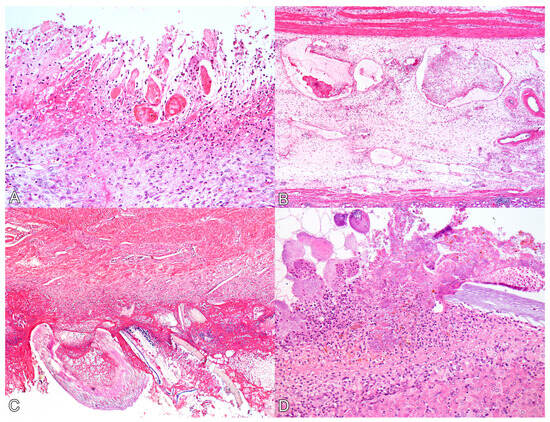

Figure 2.

Histological lesions of perforated ulcerative gastritis in swine associated with acute oral chromium exposure. (A) Stomach. There is diffuse necrosis of the glandular mucosa, characterized by loss of tissue and cellular architecture and associated with hyperemia, neutrophil infiltration, and fibrin deposition. Swine 3. HE, 200×. (B) Stomach. The submucosa exhibits marked edema, and lymphatic vessels appear ectasic and filled with fibrin thrombi. Swine 3. HE, 100×. (C) Stomach. On the serosal surface, there is marked fibrin deposition, infiltration of neutrophils, bacterial myriad, and fragments of plant fibers from the gastric content. Swine 4. HE, 100×. (D) Liver. The Glisson’s capsule shows marked fibrin deposition, neutrophil infiltration, and bacterial myriad. A plant fiber is also noted amidst the lesion. Swine 4. HE, 200×.

Histologically, the main lesions were observed in the glandular stomach. In the mucosa of the glandular stomach of all pigs, there was marked ulceration (Figure 2A), characterized by necrosis of the epithelium and tissue discontinuity, along with pronounced inflammatory infiltrate of neutrophils, deposition of fibrin, and coccobacillary bacterial myriad. The inflammatory infiltrate extended into the submucosa and muscular layers, where it was associated with severe edema and vascular thrombosis (Figure 2B). Additionally, multiple fibrin thrombi were observed within lymphatic vessels in the submucosa. The mucosa adjacent to the ulcerations exhibited marked congestion. In the mucosa of the pars esophagea (aglandular stomach) and esophagus, all animals displayed moderate and diffuse parakeratotic hyperkeratosis, accompanied by multifocal areas of erosion in the cardia (swine 1 and 4) and esophagus (swine 2 and 3).

In swine 1, 3, and 4, the duodenum exhibited multifocal areas of moderate erosion of the epithelium, characterized by necrosis of enterocytes and inflammatory infiltration of lymphocytes, plasma cells, and histiocytes in the lamina propria.

On the serosal surfaces of the stomach (Figure 2C), small and large intestines, and urinary bladder (as well as in the hepatic (Figure 2D) and splenic capsules), there was marked fibrin deposition, along with abundant plant fibers. Additionally, inflammatory infiltration of neutrophils and coccobacillary bacterial myriad were noted.